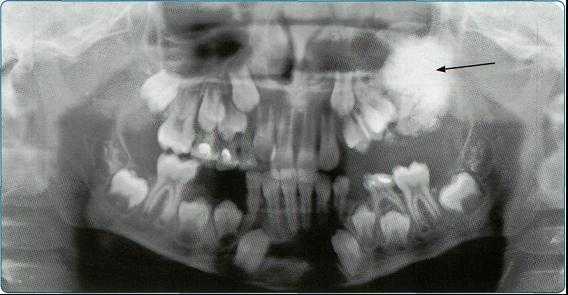

Особенно важно использовать ортопантомографию в детской стоматологии, где она не имеет конкурентов в связи с низкими дозами облучения и большим объемом получаемой информации. В детской практике ортопантомография помогает диагностировать переломы, опухоли, остеомиелит, кариес, периодонтиты, кисты, определять особенности прорезывания зубов и положение зачатков.

Одонтома чаще возникает у детей в возрасте до 15 лет. Обычно опухоли имеют небольшие размеры, протекают бессимптомно, однако могут вызывать задержку прорезывания постоянных зубов, диастемы и тремы. Опухоли большой величины могут приводить к деформации челюсти, образованию свищей.

Одонтогенная фиброма развивается из соединительной ткани зубного зачатка; чаще возникает в детском возрасте. Рост опухоли медленный; локализация - на верхней или нижней челюсти. Одонтогенная фиброма обычно бессимптомна; в некоторых случаях могут отмечаться ноющие боли, ретенция зубов, воспалительные явления в области опухоли.